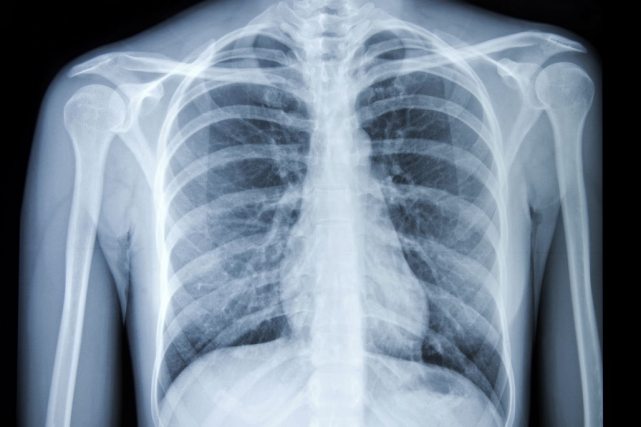

那为什么叫白肺呢?这是因为正常健康的肺,都是由通气功能正常的肺泡组成的,在X光和CT上都是透光的,并且显示为“黑色”。但如果肺部有严重的疾病(比如肺炎或者肺部肿瘤),或者有大量的胸腔积液,让健康的肺组织不再具有正常的通气和其他交换功能,肺泡组织被破坏了,这时候在X光和CT上就表现为“白色”。

健康的肺